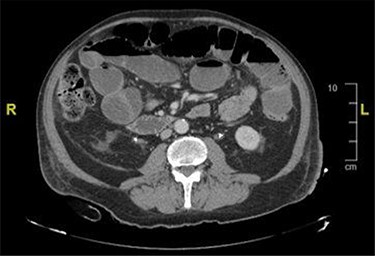

During an admission for deep vein thrombosis post lithotripsy of urethral calculi, a computed tomography (CT) of the thorax, abdomen and pelvis showed an extensive mass in the presacral region with invasion of the urinary bladder and orifices of both ureters with enlarged lower paraaortic and pelvic lymph nodes (Fig. 1). A urinary bladder biopsy obtained during a rigid cystoscopy showed an indeterminate invasive carcinoma.

CT image showing an extensive mass in the presacral region with invasion to the urinary bladder and both ureters.